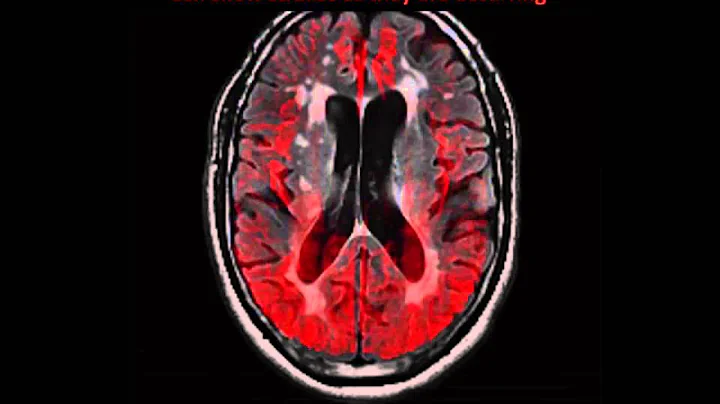

The Aging Brain

William Griffith, PhD, Regents Professor and head of the Department of Neuroscience and Experimental Therapeutics at the ...